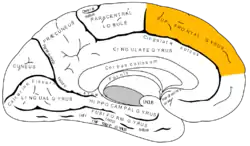

Coronal section through anterior cornua of lateral ventricles. Superior frontal gyrus is shown as yellow.

In neuroanatomy, the superior frontal gyrus (SFG, also marginal gyrus) is a gyrus – a ridge on the brain's cerebral cortex – which makes up about one third of the frontal lobe. It is bounded laterally by the superior frontal sulcus.[1]